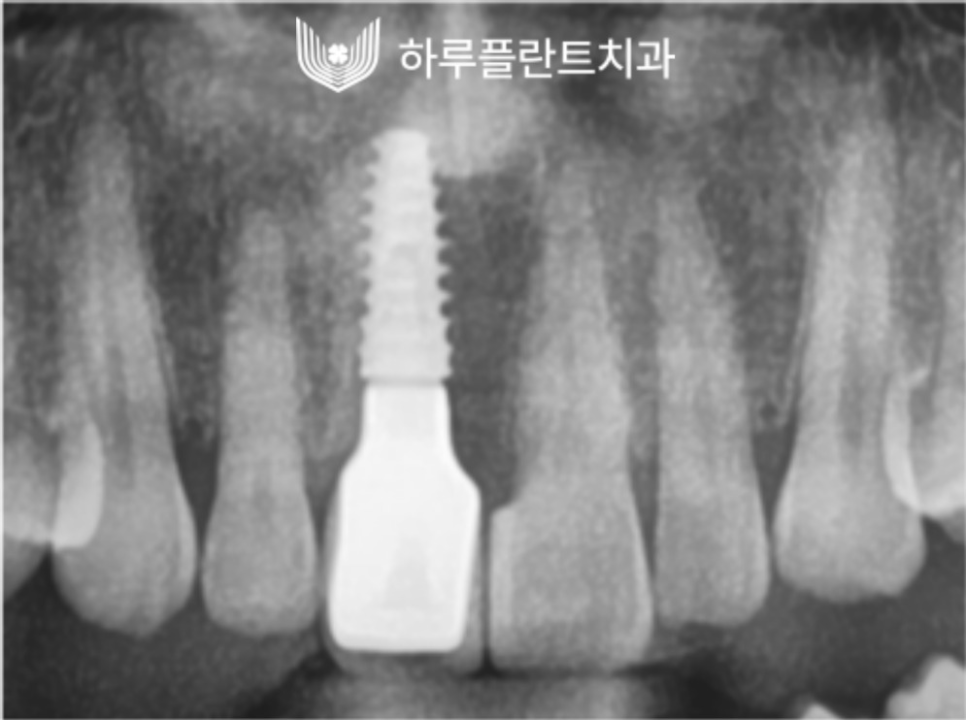

2022.12

(왼) 임플란트 보철물 최종 수복 후 촬영한 사진입니다. / (오) 보철물 수복 후 촬영한 X-ray 사진입니다.

(왼) 뼈이식을 동반한 임플란트 식립 X-ray 사진입니다. / (오) 최종 구강 내 X-ray 사진입니다.

안정적으로 정확한 방향으로 식립된

모습을 확인할 수 있으며

이렇게 잘 식립된 임플란트는

사후관리만 꼼꼼히 잘 이루어진다면

반영구적으로 사용할 수 있습니다.